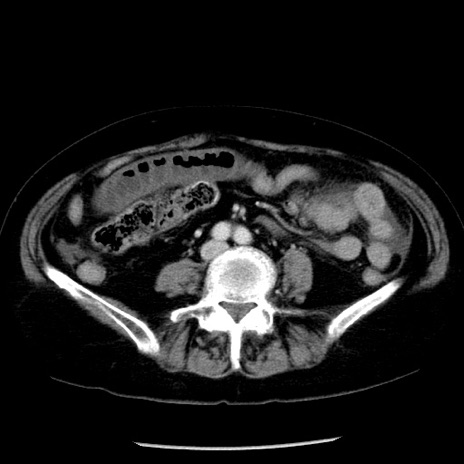

症例13(横断像)

【症例】70歳代女性

【主訴】腹痛、嘔吐

【現病歴】15時間程前(昨晩)より腹痛あり。今朝になっても症状の改善なく、嘔吐あり。腹痛も増悪あり、救急外来受診。

【既往歴】子宮癌全摘術後

【身体所見】意識清明、BP 121/72mmHg、P 74bpm、SpO2 100%(RA)、腹部:平坦・軟、腸雑音ほぼ聴取せず。下腹部・心窩部・臍左上に圧痛あり。反跳痛なし。

【データ】WBC 10600、CRP 0.15